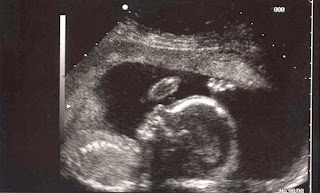

This procedure helps the doctor

to detect the possibility of genetic, metabolic or neurological disorders in

developing fetus.